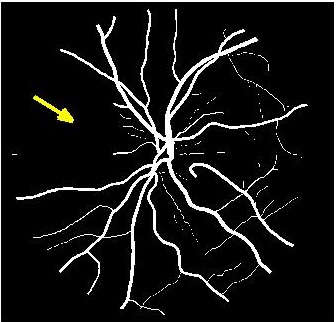

Results of fold cross validation for are presented in Table 1. Due to space constraints only SSIM values are shown for . For , performance difference of all methods is small but becomes more pronounced for higher . gives the best results for all , and the improvement over competing methods is significant as is evident from the values of Wilcoxon signed-rank tests. Figure 3 shows results of the top methods (due to space constraints) for . shows the best performance as is evident from the SR image in Fig. 3 (b) where one of the minor retinal branches (indicated by yellow arrow) is clearly visible. On the other hand the SR image by (Fig. 3 (c)) is blurry and does not clearly show this retinal branch. Other methods perform much worse, with significant blur visible for the main branches as well. Clearly, gives the closest reconstruction to the HR image of Fig. 3 (a).

![]() |

| (a) | (b) | (c) | (d) |